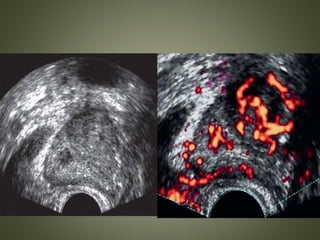

COLOR AND POWER DOPPLER IMAGING

• Detection of neovascularity associated with

cancer

• Especially attractive to find isoechoic cancer

Pitfalls

• Not all cancers are vascular.

• Capsule of the prostate is very vascular,

especially at the base and apex, and can mimic

neovascularity.